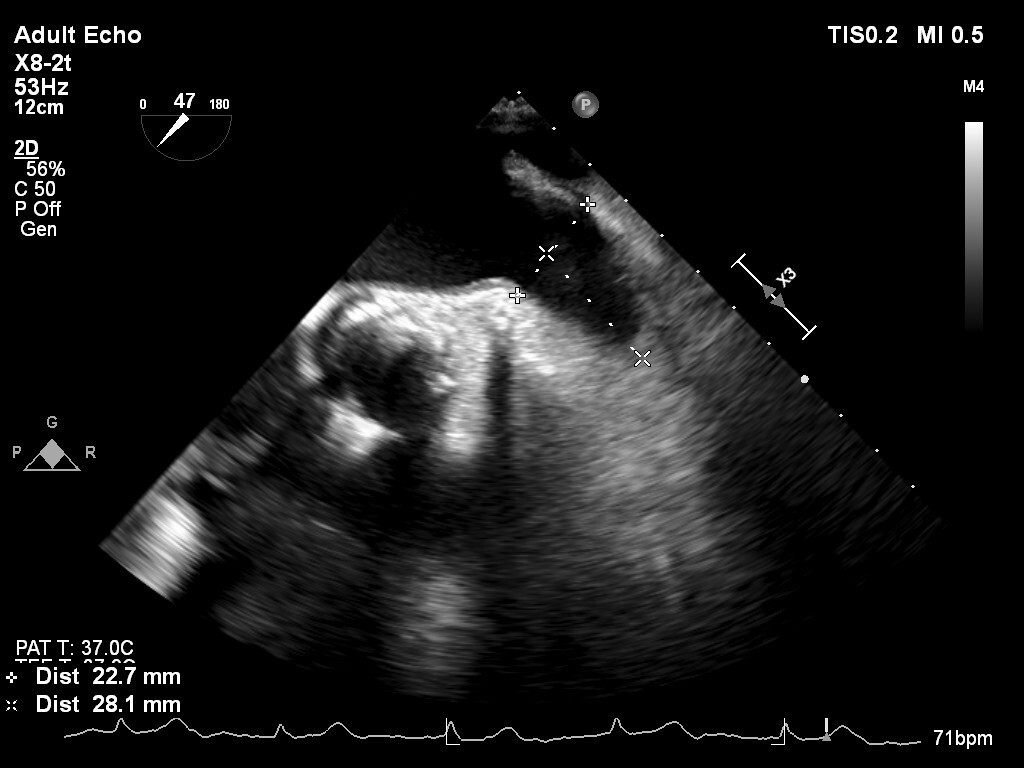

【症例】

80歳代 男性

糖尿病, 高血圧症, 脂質異常症, 持続性心房細動, 食道癌, 胃癌(2020/2), 大腸癌術後(2001,2009), 慢性腎臓病, 高度貧血, TAVI(2019/12 Sapien3 26mm), 冠動脈バイバス術後(2018/04), ラクナ梗塞

しかし出血リスク高く、今回左心耳閉鎖治療予定となる